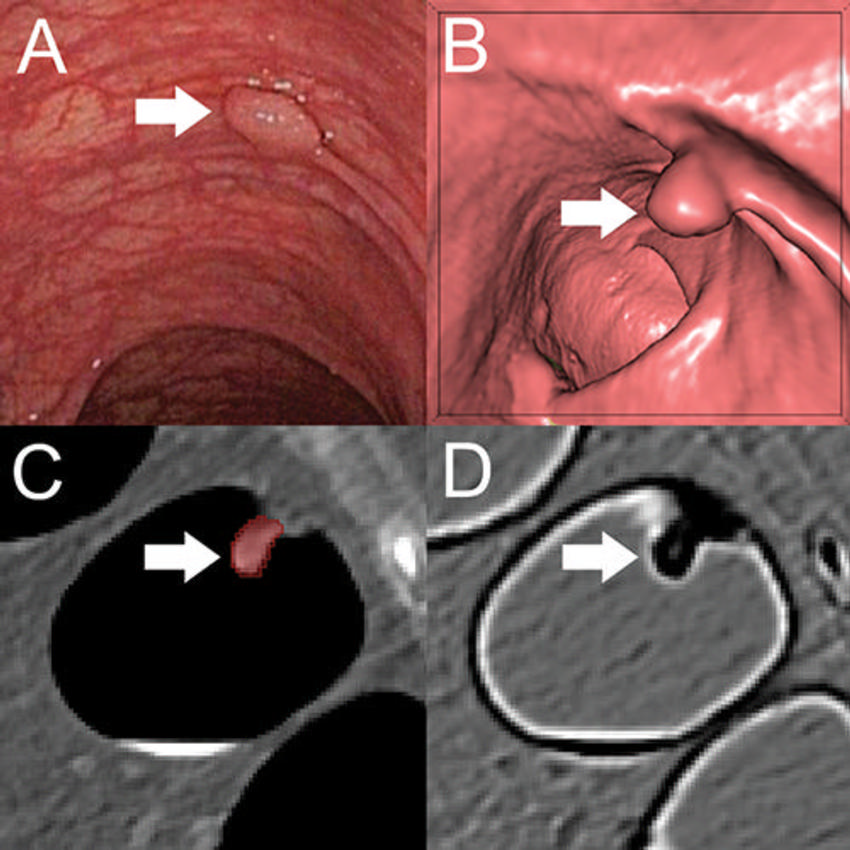

Figure 2. A, Optical colonoscopy and, B–D, CT colonography of a 9-mm polyp (arrow) in the descending colon of a 78-year-old woman. B, Virtual fly-through three-dimensional reconstructions were used for exact polyp localization. C, Manual polyp segmentation was performed in multiplanar two-dimensional CT colonography images. D, CT colonography images were preprocessed for image feature extraction by application of a dedicated filter.